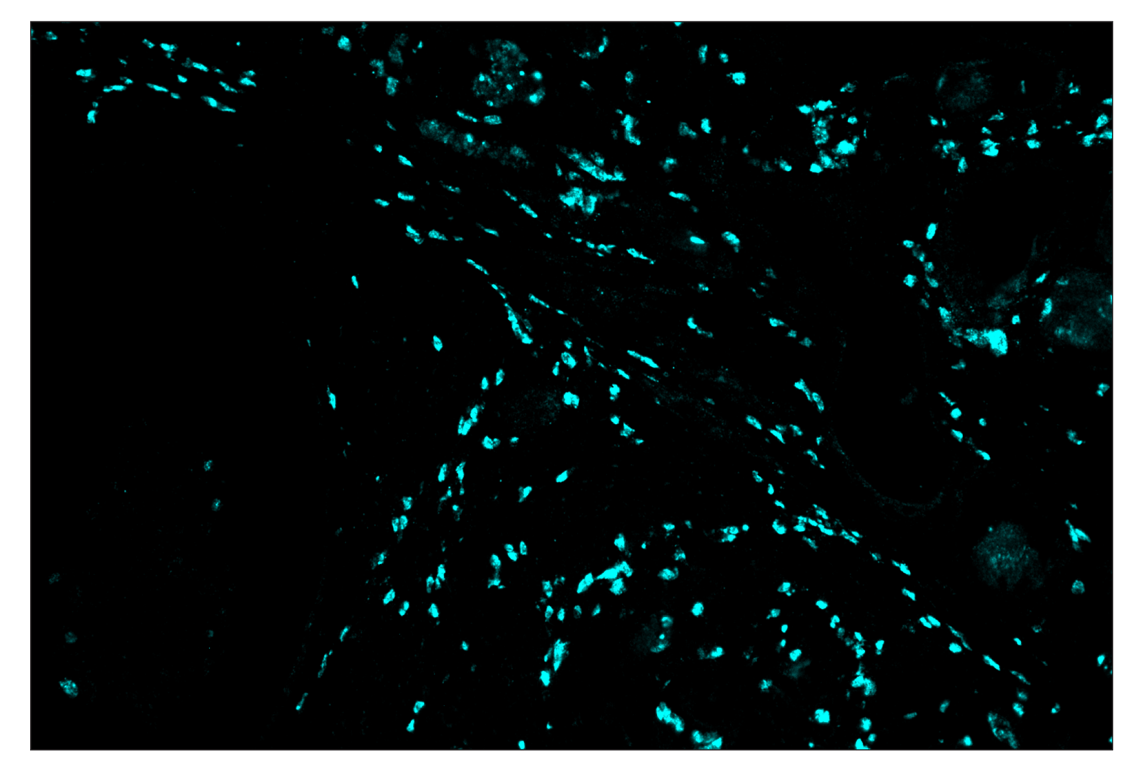

SignalStar™ multiplex immunohistochemical analysis of paraffin-embedded human lymph node using CD19 (Intracellular Domain) (D4V4B) & CO-0054-647 SignalStar™ Oligo-Antibody Pair #96289 (red) and Arginase-1 (D4E3M) & CO-0075-750 SignalStar™ Oligo-Antibody Pair #97934 (cyan). All fluorophores have been assigned a pseudocolor, as indicated.

Immunohistochemistry Image 2: Arginase-1 (D4E3M) & CO-0075-750 SignalStar<sup>™</sup> Oligo-Antibody Pair